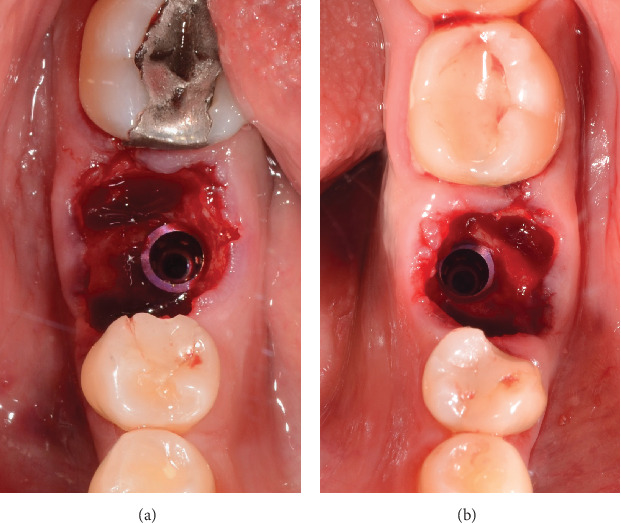

Background: The management of peri-implant tissue seeks to meet the aesthetic expectations of patients, with a smaller number of procedures that favor the development and maintenance of healthy peri-implant soft tissue. The customized healing abutment technique on immediate implants has demonstrated numerous functions for the success of restorations on implants. Objectives: The objective of the study is to analyze the biological aspects of the customized healing abutment using PEEK and flowable composite to condition the peri-implant tissues by presenting a clinical case of a patient from the oral surgery service of Pontificia Xavierian University. Case Report: A patient underwent the placement of two postextraction implants and customized healing abutments in the posteroinferior area. Discussion: This technique is aimed at maintaining the volume of keratinized mucosa and creating an emergence profile for the future prosthesis and reducing the risk of peri-implantitis. The development of healthy peri-implant soft tissues is essential to achieve the aesthetics and biological success of implant-supported restorations in all stages of healing and tissue maturation, and the abutment is essential because it allows a biological seal that protects the bone tissue. Conclusion: It was demonstrated that the use of the customized healing abutment with PEEK and flowable composite immediately after implant placement after dental extraction keeps the volume of the soft and hard tissues around the implants at the time of definitive rehabilitation.